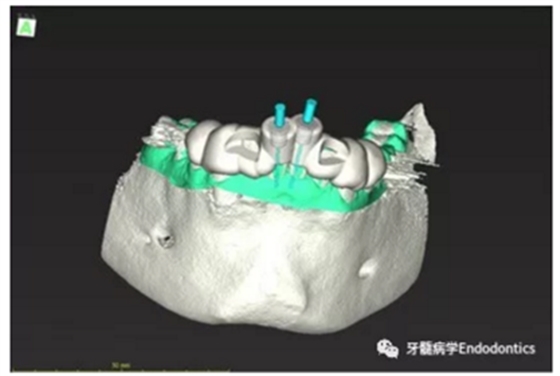

31、41叩痛明顯,牙冠變色(圖1)。溫度和牙髓電活力測(cè)試無(wú)反應(yīng)。兩張從不同角度拍攝的x線(xiàn)片顯示,相對(duì)于側(cè)切牙,雙側(cè)下中切牙都有嚴(yán)重的根管鈣化(圖2)。41有明顯根尖周暗影,31根尖周暗影不明顯。為進(jìn)一步證實(shí)31是否存在根尖周病變,同時(shí)精細(xì)觀(guān)察31、41的復(fù)雜結(jié)構(gòu),根據(jù)歐洲牙髓病學(xué)會(huì)CBCT應(yīng)用指南(2014),對(duì)患牙拍攝小視野、高分辨率CBCT。CBCT影像證實(shí)31、41均伴有根尖周炎和嚴(yán)重的根管鈣化(圖3)。距離根尖4mm可見(jiàn)根管影像。 由于患牙根管解剖結(jié)構(gòu)較為復(fù)雜,筆者決定使用特殊設(shè)計(jì)的微型鉆頭(直徑0.85mm)進(jìn)行“數(shù)字化導(dǎo)航牙髓治療”。 因此對(duì)下頜進(jìn)行口內(nèi)掃描(圖4)。用coDiagnostixTM軟件(Dental Wings Inc.,Montreal,Canada)將CBCT和口內(nèi)掃描的數(shù)據(jù)進(jìn)行處理,該軟件主要用于引導(dǎo)種植。通過(guò)該軟件對(duì)兩個(gè)掃描圖像進(jìn)行疊加后,虛擬鉆頭尖端沿牙長(zhǎng)軸對(duì)準(zhǔn)根管下段可見(jiàn)部分(圖5)。三維檢查虛擬鉆的正確位置。

圖5.虛擬設(shè)計(jì)的微創(chuàng)根管入路。虛擬鉆針的尖端能到達(dá)鈣化根管X線(xiàn)影像中的可見(jiàn)部分。

圖6.設(shè)計(jì)導(dǎo)板。